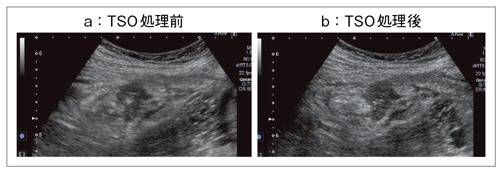

(1)TSO

TSO(Tissue Specific Optimization)は,生体特性の違いによる方位分解能の劣化を抑え画質の向上を図る機能だが,図1はそれを消化管に適応した画像である。盲腸がんの回腸末端浸潤例のオリジナル画像(図1 a)とTSO処理をした画像(図1 b)である。TSO処理した画像では,盲腸から回腸末端への浸潤の様子が正確に確認できる。Beam演算を補正することで,消化管も明瞭な描出が可能なことから,TSOは非常に有用であると言える。

図1 TSO画像(盲腸がん)